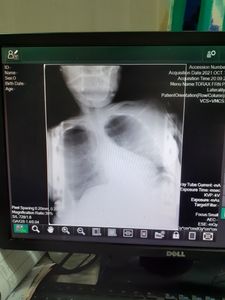

A campanha pela a qual foi criado é importante para reverter o estado debilitante que se encontra maria, no quadro de escóliose dorsal que precisa passar por cirurgia.

Ao longo da vida de Mercy, ela sempre é seus sempre passavam por problemas financeiros e devido a situação vulnerável que se encontra a filha tinha caso de escóliose não muito avançada durante a infância, porem ao passar os anos por falta de remediação a situação se agravou tendo até prejudicado vias respiratórias

Com o valor arrecadado pela comunidade, será custeado todo o tratamento desde exames pré-operatórios até a fazer da cirurgia em si que precisa de muita cautela e trabalhar de profissionais da medicina, sendo assim ficou incapaz de ser orçada pelo sistema público de saúde, nesse caso as únicas alternativas era paga pelo tratamento total de R$25.000

Cirurgia urgente de escóliose dorsal